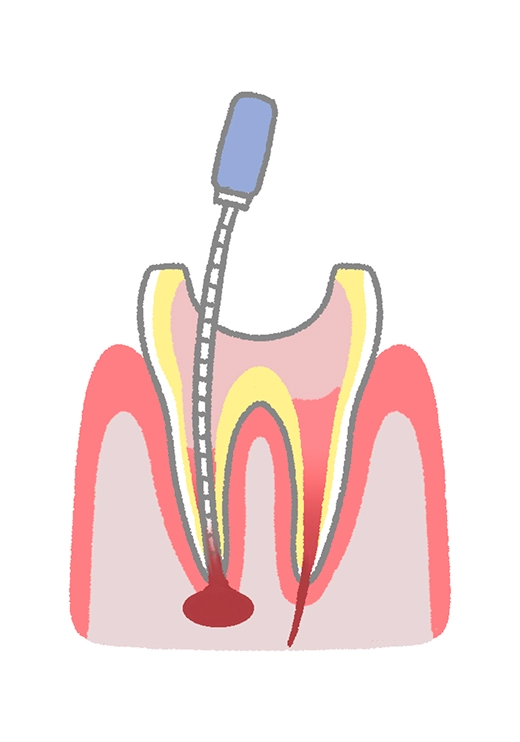

C3〜C4の深い虫歯では、歯を残すために根管治療が必要となります。治療では、感染した歯髄を丁寧に取り除き、根管の内部を洗浄・消毒して薬剤で密封します。再感染を防ぎ、抜歯を避けながら歯をできるだけ長く保つことを目指します。

虫歯が深く進行し、歯髄に細菌が及んでいる場合、まず感染した神経や血管を取り除きます。これにより痛みや炎症を取り除き、治癒の土台を整えます。